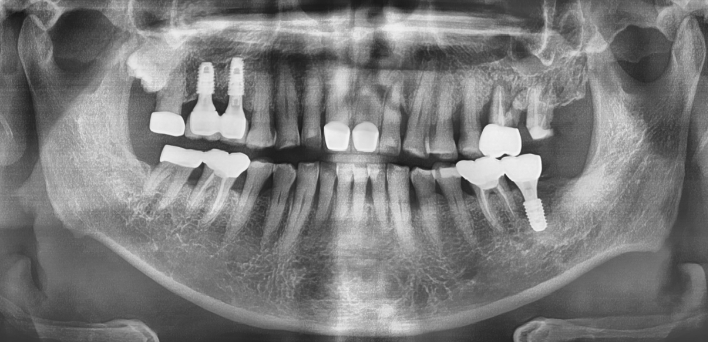

임플란트 : 손 ** 님 (50대)

치아가 있다는게, 아직도 정말 꿈만 같아요.

Before Before

2020.02.30

After After

※ 더서울치과의원은 의료법을 준수하며 위 케이스는 실제 환자의 동의를 얻은 사례로 치료 전, 후가 동일한 환경에서 촬영되었습니다.

환자 케이스에 따라 부작용이 발생할 수 있습니다. 이 부분은 의료진의 충분한 상담과 체크를 통해 예방하고 줄일 수 있습니다.

[임플란트 부작용] 수술 후 관리가 소홀할 경우 출혈, 주위염 등의 부작용이 발생할 수 있어 구강 위생을 철저히 유지하고, 정기적인 검진을 통해 상태를 점검하는 것이 중요합니다.

환자 특징

환자 특징01무치악 상태

환자 특징02수년간 무치악으로 지내심

임플란트가 불가능할것이라

생각하고 내원

위, 아래 6개씩 식립

디지털 풀아치 임플란트